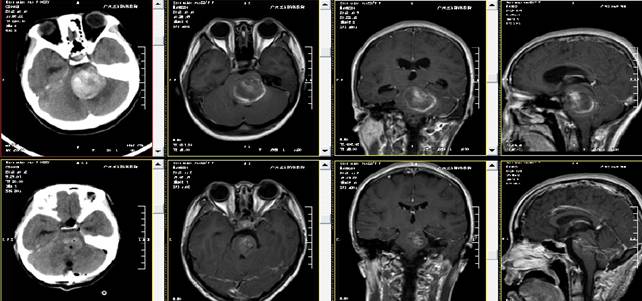

■ 术前术后对比。

入院后查头颅MRI示:

1.脑干血肿形成(出血量约为30ml),待排血管畸形;

2.幕上梗阻性脑积水;

3.MRV:左侧横窦及直窦未见显示,上矢状窦中前段信号欠均匀;4.DTT(白质纤维束三维重建)检查:病变内未见纤维束,周围纤维束受推压,左侧皮质脊髓束病变以下节段未见显示。

术后病理结果回报:符合动静脉畸形并血肿形成。复查头颅CT、MRI呈术后改变。